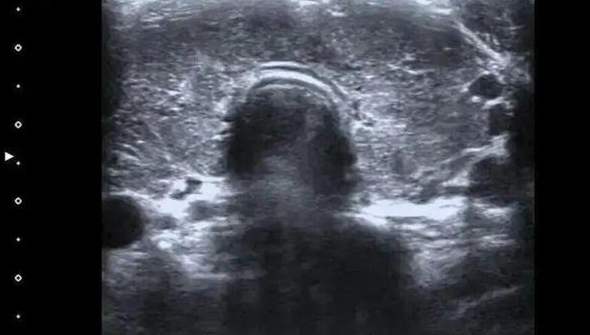

更为致命的是,陈女士的病史中潜藏着20年的甲状腺功能亢进症(甲亢),而她在过去一年里却自行停药。医生在检查中发现,游离T3和游离T4的数值分别超出正常值的三倍和四倍,促甲状腺激素几乎测不出。这一系列数据如同惊雷,宣告了她的甲状腺毒症已达到极其严重的程度,心脏的射血分数仅为40%,远低于正常水平。